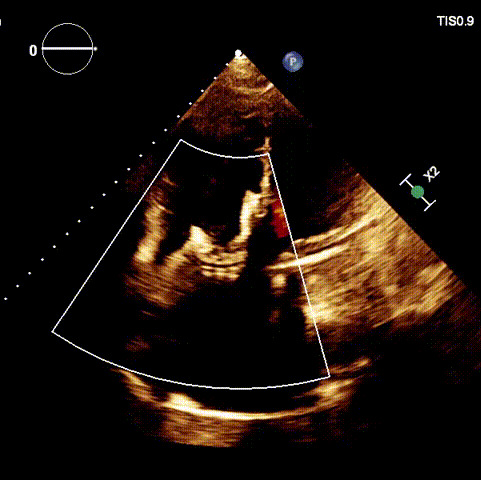

術后超聲

近日,廈門大學心血管病醫院王焱教授帶領的結構性心臟病團隊,成功應用LuX-Valve Plus經血管三尖瓣置換系統,為一例高危三尖瓣重度反流患者開展經血管三尖瓣置換手術。此次手術系LuX-Valve Plus人工瓣膜在福建省的首例植入,手術過程順利,術后患者三尖瓣反流顯著改善,標志著由葛均波院士團隊作為主要研究者的LuX-Valve Plus經血管三尖瓣置換系統全國多中心臨床研究的再一次成功實踐,為三尖瓣介入治療的醫學循證打下了夯實的基礎。 、